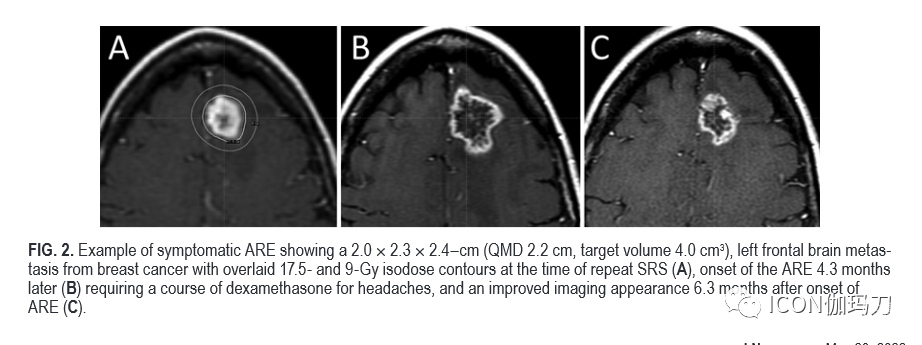

图2。ARE症状的例子显示2.0x2.3x2.4厘米(QMD 2.2厘米,靶体积4.0cm3),对来自乳腺癌的左额脑转移瘤,重复SRS 治疗时以17.5 - 和9-Gy等剂量线轮廓覆盖(a), 4.3个月后开始出现ARE(B)需要一个疗程的地塞米松治疗头痛、ARE发病6.3个月后影像学表现改善(C)。